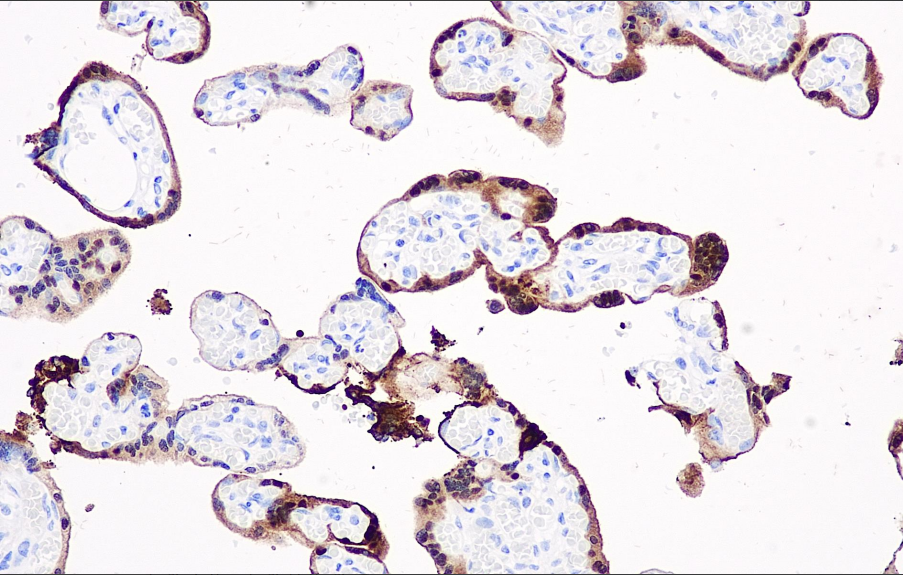

Positive control: Placenta

S100P belongs to the S-100 protein family, whose family proteins are expressed in most cells and may be involved in cell division and differentiation. S100P is highly expressed in the placenta. In pancreatic ductal carcinoma, nearly 100% of tumor cells express S100P positively, whereas benign ducts and glands do not express it. The S100P antibody is highly useful for distinguishing between ductal carcinoma and benign ductal lesions in pancreatic biopsy studies. S100P is expressed in cholangiocarcinoma but not in normal cholangiocarcinoma epithelium or reactive hyperplastic cholangiocarcinoma epithelium, aiding in the differentiation of benign from malignant tissue during cholangiocarcinoma biopsy.

The S100P antibody reagent specifically binds to the S100P molecular antigen. The immunohistochemistry kit containing the S100P antibody reagent is suitable for the auxiliary diagnosis of pancreatic cancer, cholangiocarcinoma, and certain adenocarcinomas.